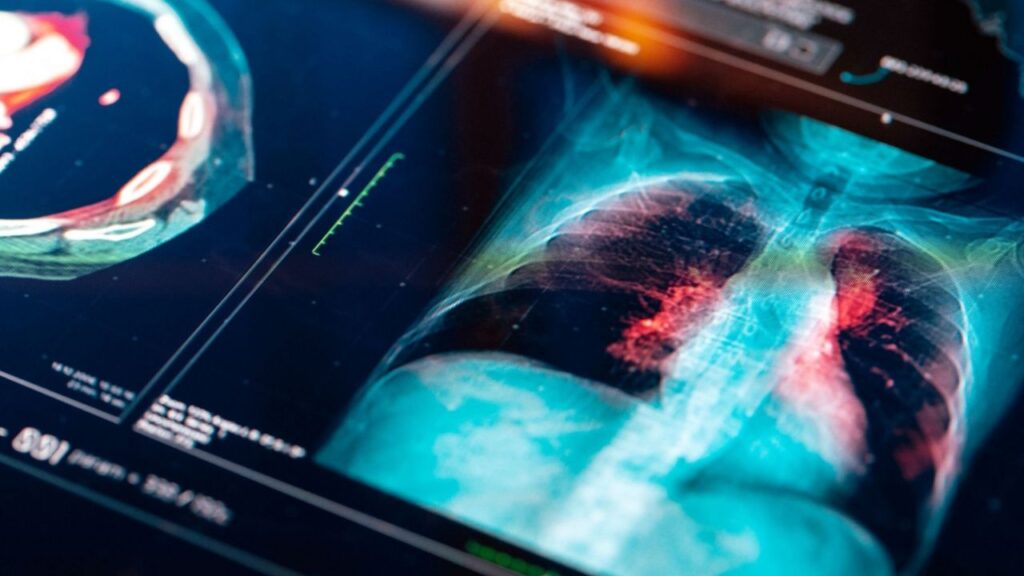

A pneumonia é uma infecção que se instala nos pulmões, podendo acometer os alvéolos pulmonares. Deles saem as ramificações terminais dos brônquios (órgãos que, quando inflamados, causam a bronquite) e, muitas vezes, os interstícios — espaço entre os alvéolos. A doença se desenvolve devido à penetração de agente infecciosos, como vírus, bactérias, fungos ou substâncias químicas, no espaço alveolar, onde acontece a troca gasosa.

Por isso, essa região precisa estar sempre limpa, longe de substâncias que possam interferir no contato do sangue com o ar. Quando alvéolos pulmonares e bronquíolos se encontram inflamados, os pulmões ficam comprometidos e não funcionam corretamente.